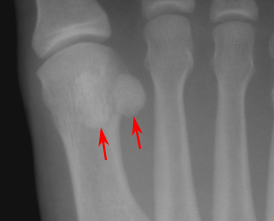

| Сесамовидные кости в области дистального отдела первой плюсневой кости | |

- стопа — две сесамовидные кости в области соединения первой плюсневой кости с первым пальцем (внутри сухожилия короткого сгибателя большого пальца стопы)[2].